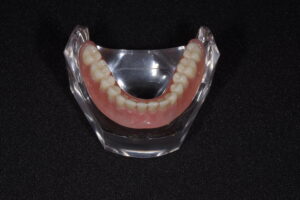

最終的にはこんなイメージ!!!

・会話や食事の際に外れる

・噛んだら痛くて食事が満足にできない

・入れ歯が大きいのが嫌なので、小さくできないのか

などなど、様々な問題点を解決してくれるインプラント併用の入れ歯。